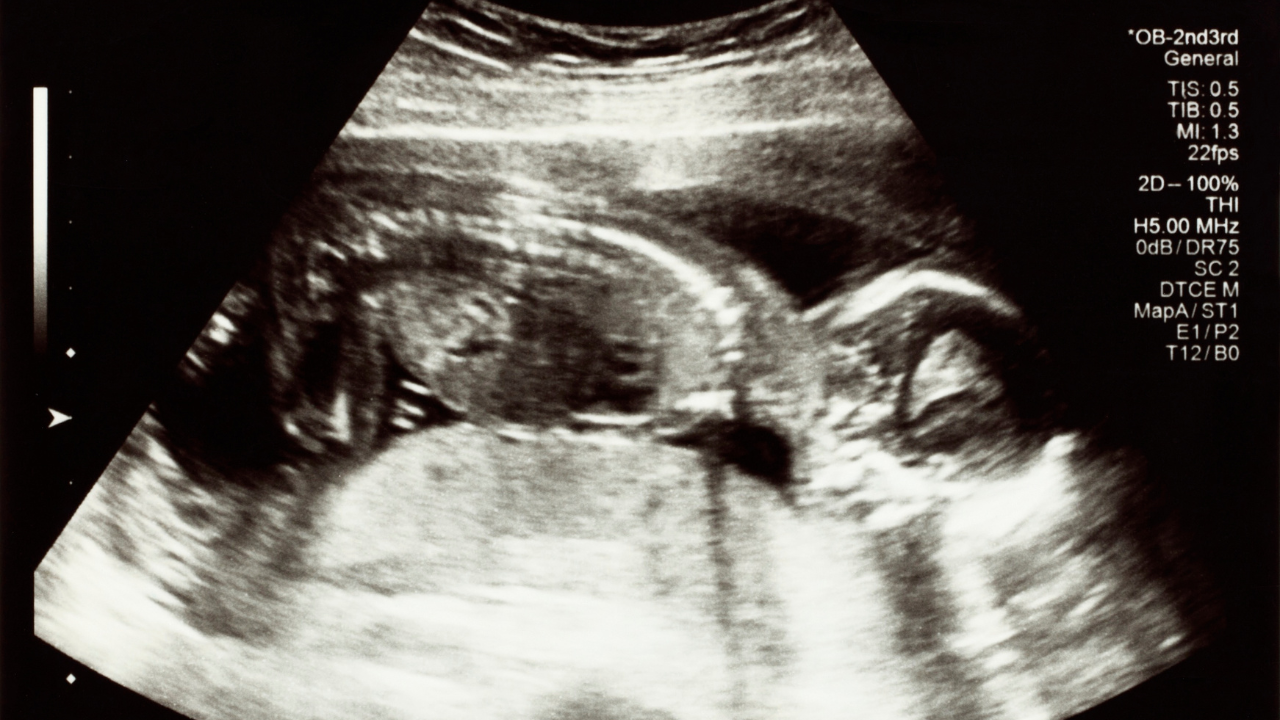

Trong tam cá nguyệt thứ hai, thai nhi không chỉ lớn hơn mà còn bắt đầu hình thành các tư thế quan trọng trong tử cung. Việc biết được vị trí thai nhi trong bụng mẹ 3 tháng giữa giúp dự đoán phương pháp sinh nở phù hợp, đồng thời phát hiện sớm những ngôi thai bất thường có thể gây khó khăn trong quá trình chuyển dạ. Từ đó, mẹ bầu và bác sĩ có thể lên kế hoạch chăm sóc và theo dõi sức khỏe thai kỳ một cách tốt nhất.

Trong giai đoạn 3 tháng giữa thai kỳ, thai nhi thường nằm ở vị trí trong tử cung, phía trên xương mu và bắt đầu phát triển lớn hơn. Lúc này, tử cung của mẹ đã mở rộng và thai nhi có thể nằm ở vùng bụng dưới, gần rốn. Tùy thuộc vào sự phát triển của thai nhi và cơ địa của mẹ, vị trí cụ thể có thể thay đổi một chút. Thai nhi cũng bắt đầu có nhiều chuyển động hơn, đôi khi mẹ có thể cảm nhận được bé đạp hoặc di chuyển.

Giai đoạn 3 tháng giữa thai kỳ, trung bình thai nhi nặng khoảng 0,8 - 0,9 kg và dài khoảng 36 - 37 cm. Sự tăng trưởng nhanh về chiều dài và cân nặng khiến các cử động của bé trở nên rõ ràng hơn, giúp mẹ dễ dàng xác định vị trí của con trong bụng. Thông thường, trong 3 tháng giữa, thai nhi thường nằm với phần đầu hướng xuống dưới, gần âm hộ hoặc dưới rốn mẹ. Tuy nhiên, tùy thuộc vào tư thế và không gian trong tử cung, thai nhi có thể nằm ở nhiều vị trí khác nhau.

Hiểu rõ vị trí của thai nhi trong bụng mẹ ở 3 tháng giữa thai kỳ là bước quan trọng giúp mẹ bầu chuẩn bị cho hành trình sinh nở sắp tới. Việc theo dõi thường xuyên qua cảm nhận thai máy và các lần siêu âm định kỳ sẽ giúp phát hiện sớm các bất thường, đảm bảo quá trình mang thai diễn ra an toàn. Đồng thời, việc nắm bắt vị trí thai còn giúp mẹ yên tâm, tận hưởng trọn vẹn giai đoạn phát triển kỳ diệu của con yêu trong bụng.